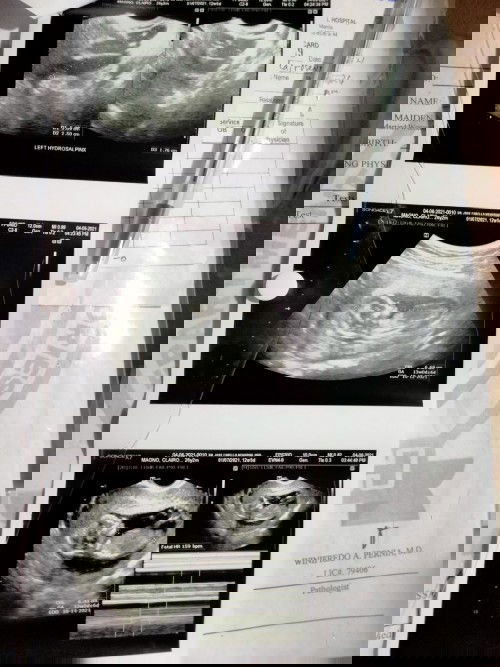

Good evening po, heto na po result ng trans v/ transabdominal ultra ko insert ko po sa baba ung pic. Pasuyo po ako kung cnu po mkaintindi nito kung ilan buwan ba baby ko sa tummy ko po.. Ako po ung nagpost nung nkaraan na sa unang trans v ko po nung feb eh wla pa dw laman pero nung april 6 meron na po at buo na ung baby mula ulo gang paa. Thank you po sa apps na to at sa mga mommies dto..